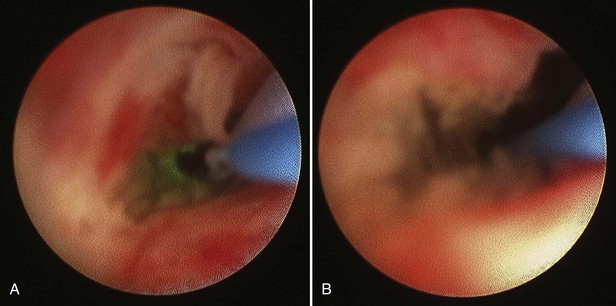

General anesthesia is used in order to minimize patient movement during ureteroscopy and the subsequent incision of the UPJ. In preparation for the endopyelotomy, a retrograde pyelogram is performed under fluoroscopic control at the outset of the procedure. A hydrophilic guidewire is passed cystoscopically under fluoroscopic control and coiled in the pyelocalyceal system. The cystoscope is then withdrawn and exchanged for the semirigid ureteroscope. The ureteroscope is passed alongside the guidewire to the level of the UPJ. If the distal ureter is too narrow to allow easy passage of the ureteroscope, the intramural ureter can be dilated using a 5-mm balloon or a No. 9- or 10-Fr “introducing” catheter. If the ureter is still too narrow at any point to easily accommodate the ureteroscope, then an internal stent is placed and the procedure postponed for 5 to 10 days to allow “passive” ureteral dilatation. Alternatively, an actively deflecting flexible ureteroscope may be used, and in most cases a ureteral access sheath is quite useful. The sheath allows for rapid transfer of the ureteroscope for assessment of the UPJ. Once the flexible ureteroscope is passed to the UPJ, a 200-µm holmium fiber is placed through the working channel and the UPJ incised in the appropriate location, as suggested by the radiographic studies (Figs. 41-10 and 41-11).

Figure 41–10 Flexible ureteroscopic endopyelotomy using holmium laser, demonstrating endoscopic view of the ureteropelvic junction (inset). A safety wire is in place, and the ureteroscope is passed through a ureteral access sheath as a lateral incision is being made under endoscopic view, using holmium laser fiber. A properly sited, complete incision is straightforward with this direct visualization technique.

Figure 41–11 A, Endoscopic view of ureteropelvic junction (UPJ) stenosis with safety wire and laser fiber during incision. B, Following incision, note full-thickness incision and minimal bleeding with capacious UPJ.

Once the UPJ is reached with the ureteroscope, the renal pelvis is drained to assist movement across the UPJ during the incision. When using a semirigid ureteroscope, the 200- or 365-µm holmium laser fiber is inserted through the working channel as the ureteroscope is positioned at the proximal extent of the UPJ or in the renal pelvis itself. At a setting of 0.8 to 1.2 Joules and a frequency of 10 to 15 Hz, the UPJ is incised, usually in a posterolateral direction, while the ureteroscope is withdrawn back down across the UPJ. This procedure is repeated, and the incision gradually deepened to extend into the peripelvic and periureteral retroperitoneal space. Because this is done gradually and under direct vision, any visualized vessels, and thus potentially significant bleeding, are usually avoided.